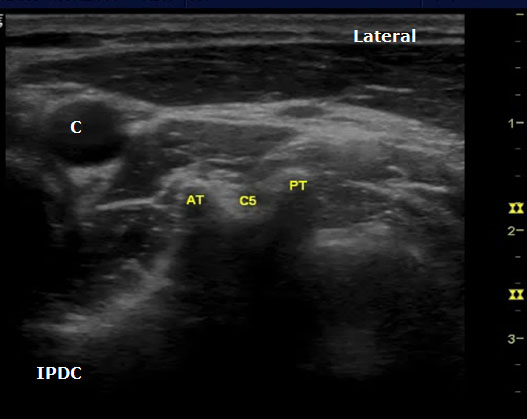

The sonoanatomy of the anterior and posterior tubercles associated with the transverse processes of the C4, C5, C6, and C7 vertebrae are used to identify their respective cervical nerve roots. The C7 vertebral body demonstrates an absent or rudimentary anterior tubercle with a prominent posterior tubercle (Figure 7). The anterior and posterior tubercles are seen as hyperechoic outlines with associated acoustic shadowing (hypoechoic area below). C6 has a sharp and prominent anterior tubercle and a shorter posterior tubercle. The nerve roots are viewed as homogeneous oval hypoechoic structures that exit through the transverse processes of the corresponding vertebral level. For example, the C6 nerve root will be seen between the anterior and posterior tubercles of the transverse process of C6 (Figures 8 & 9). The nerve roots differ in appearance from peripheral nerves below the clavicle which have a more hyperechoic appearance. As the transducer progresses to the more cephalad nerve roots, the anterior and posterior tubercles assume similar size characteristics (Figure 10) that have been referred to as the “2 humped camel sign.”[17] In approximately 90% of cases at the C7 level (Figure 7), the vertebral artery can be visualized prior to its entrance into the foramen at the C6 level.[10][18] Other important structures to visualize in the neck to assist with orientation include the thyroid, internal carotid artery, and jugular vein.

Figure 10. An axial image at the C5 level demonstrating the typical sonoanatomy of the anterior and posterior tubercles. AT = Anterior Tubercle; C = Carotid Artery; C5 = C5 Nerve Root; PT = Posterior Tubercle.

Ultrasound Technique for Cervical Nerve Root Block

The spinal nerve roots are identified on the basis of different morphologies of the transverse processes of each vertebral body. The patient is positioned in either the lateral decubitus position with visualized side up or in the supine position. In the supine position the cricoid cartilage should be palpated as a C6 landmark. Position a high-frequency linear array ultrasound transducer (5 to 12 MHz) lateral to this location. The transducer is applied transversely to the lateral aspect of the neck, and a short axis view is obtained. The carotid artery, internal jugular, vein, and thyroid should be identified. In the supine position the transducer is situated and moved laterally in the axial direction until the transverse processes are identified. The transverse processes are lateral to the carotid artery.

The level of the cervical spine is identified by the corresponding morphology of the transverse processes. At the C6 level the prominent anterior tubercle will be visualized with the longus colli muscle medially. The ultrasound transducer should be moved in a craniocaudal direction to further confirm the appropriate cervical level. The C7 level will have a prominent posterior tubercle, and the vertebral artery will be visualized medially in a majority of cases. As the transducer is moved cephalad from the C6 level, the anterior and posterior tubercles will assume a similar shape with the nerve root lying in between. In cases in which the identification of the cervical level is challenging, other sonoanatomy clues can be utilized.